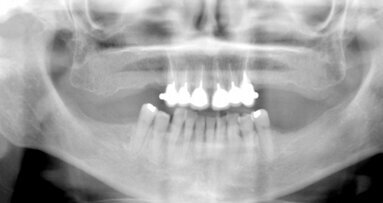

La terapia con ozono ha demostrado que tiene un amplio rango de aplicaciones terapéuticas, principalmente como un procedimiento adyuvante que mejora sobre manera los resultados de la periodoncia, ortodoncia, implantología y la estética.

Así, esta tecnología permite aplicar de una forma segura y eficiente ozono en cavidades dentarias, fosas, puntos y surcos, endodoncias, cirugía, periodoncia, estomatología, ortodoncia e implantología.

El Dr. Raúl Moggiano, gerente de GO3, explica la funciones del GO3 Advance. Moggiano afirma que, gracias a los efectos que tiene el ozono como desinfectante y reconstituyente celular, el dispositivo es útil y eficiente para tratar problemas periodontales, ortodóncicos, cariológicos y endodónticos, al igual que para realizar procedimientos de aclaramiento dental y para minimizar la sensibilidad dentinaria.

Combinado con agua bidestilada, el ozono es un excelente desinfectante y anti-inflamatorio local, que se utiliza para lavajes de tejidos previos a tratar o ya tratados, en alveolitis y cirugía implantológica, cirugía en general, al igual que para el tratamiento de la halitosis y como enjuagatorio en general.